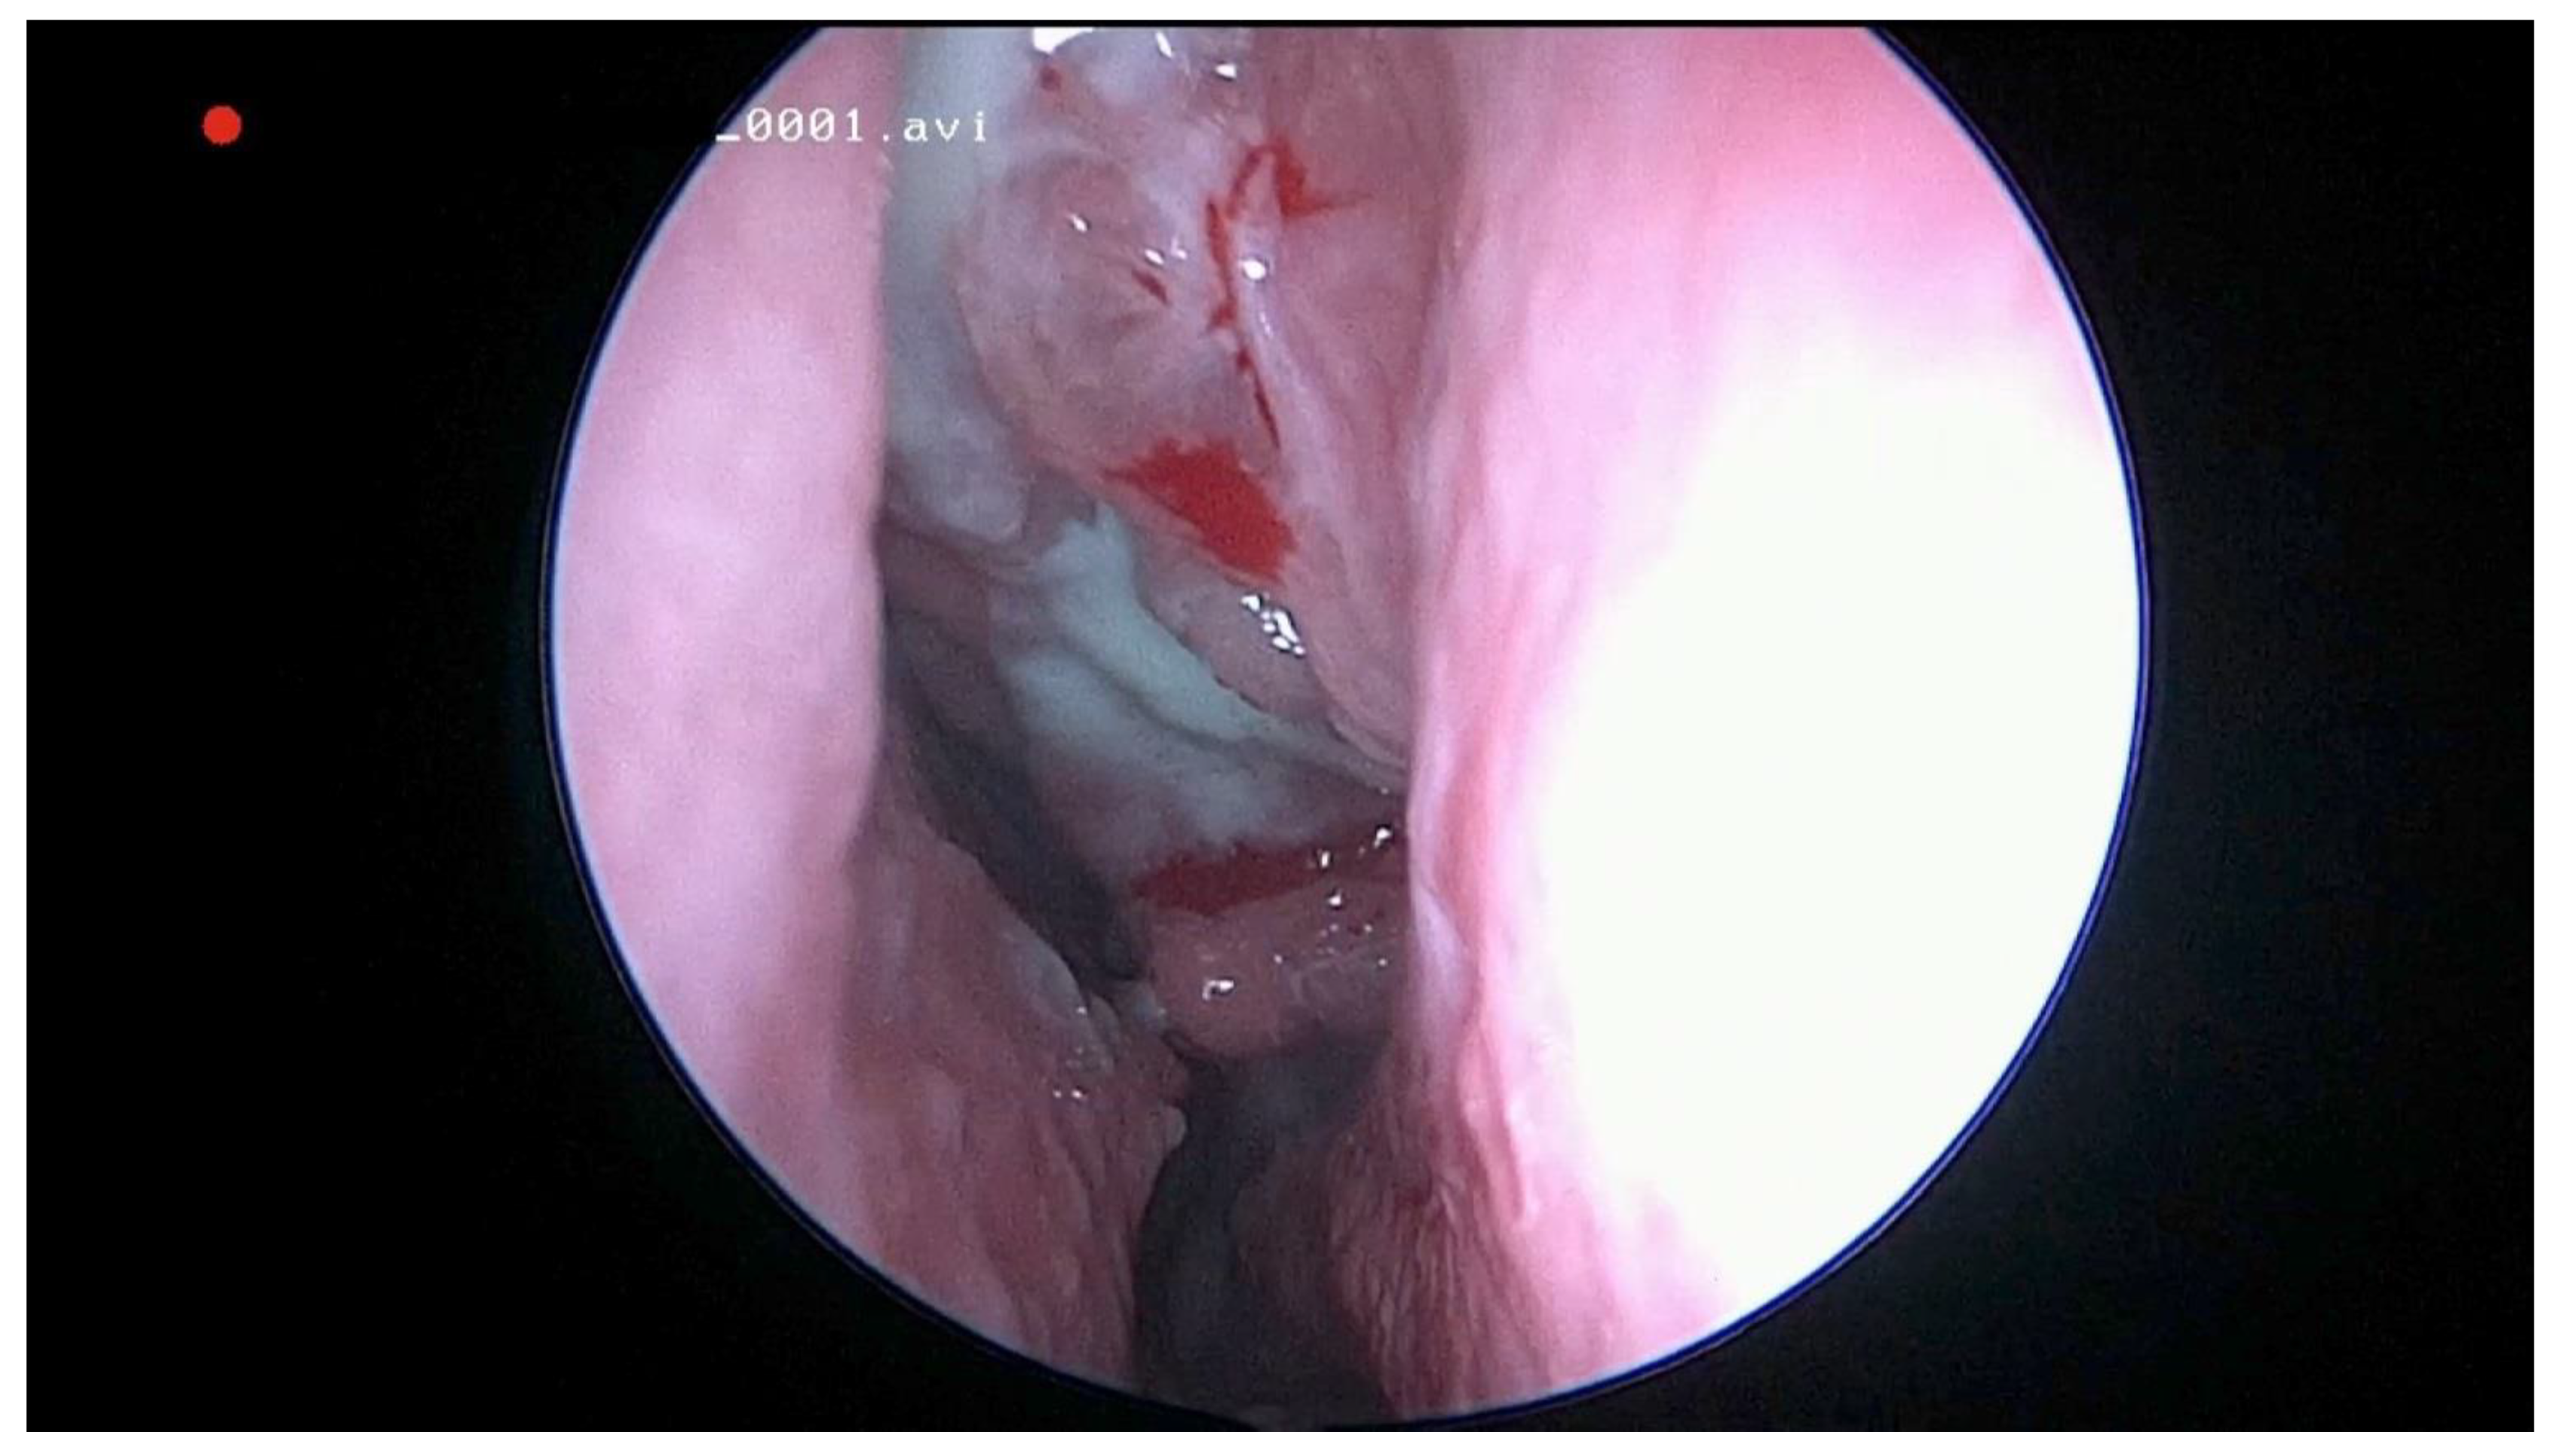

Figure 1.

Endoscopic view of the left middle meatus with polypoid tissue and purulent drainage from the maxillary sinus in a patient with odontogenic sinusitis.